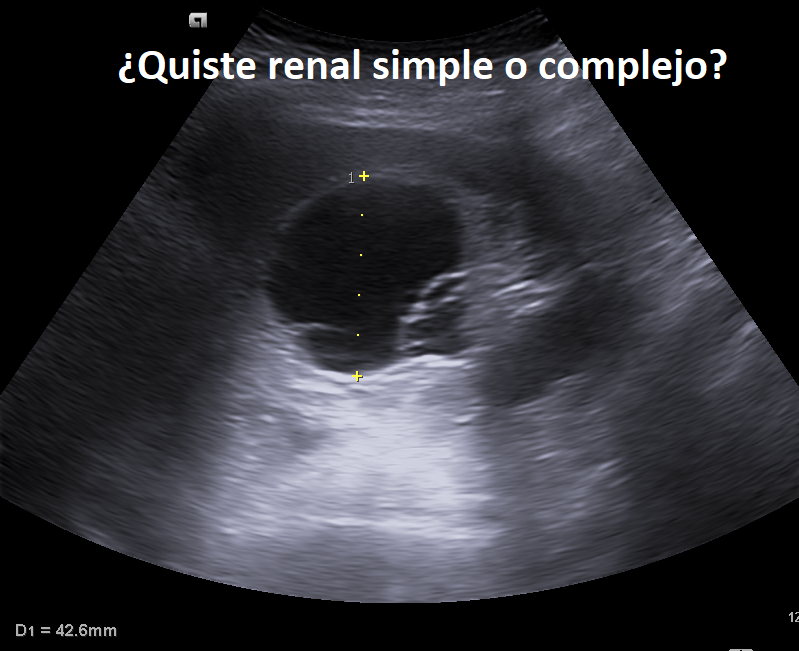

Compañeros de la ecografía clínica, si encontráis esto como hallazgo incidental, ¿cómo lo catalogaríais?

¿Quiste renal simple o complejo?

#POCUS #Ecosemfyc

@EcosemfyC Quiste renal complejo, ya que sus bordes no son regulares y tiene elementos ecogénicos en su interior

¿Cuáles son los síntomas que puede presentar este paciente?

A. Dolor lumbar

B. Hematuria

C. Asintomático

D. Todas pueden ser ciertas

🤓 #POCUS #EcosemFYC